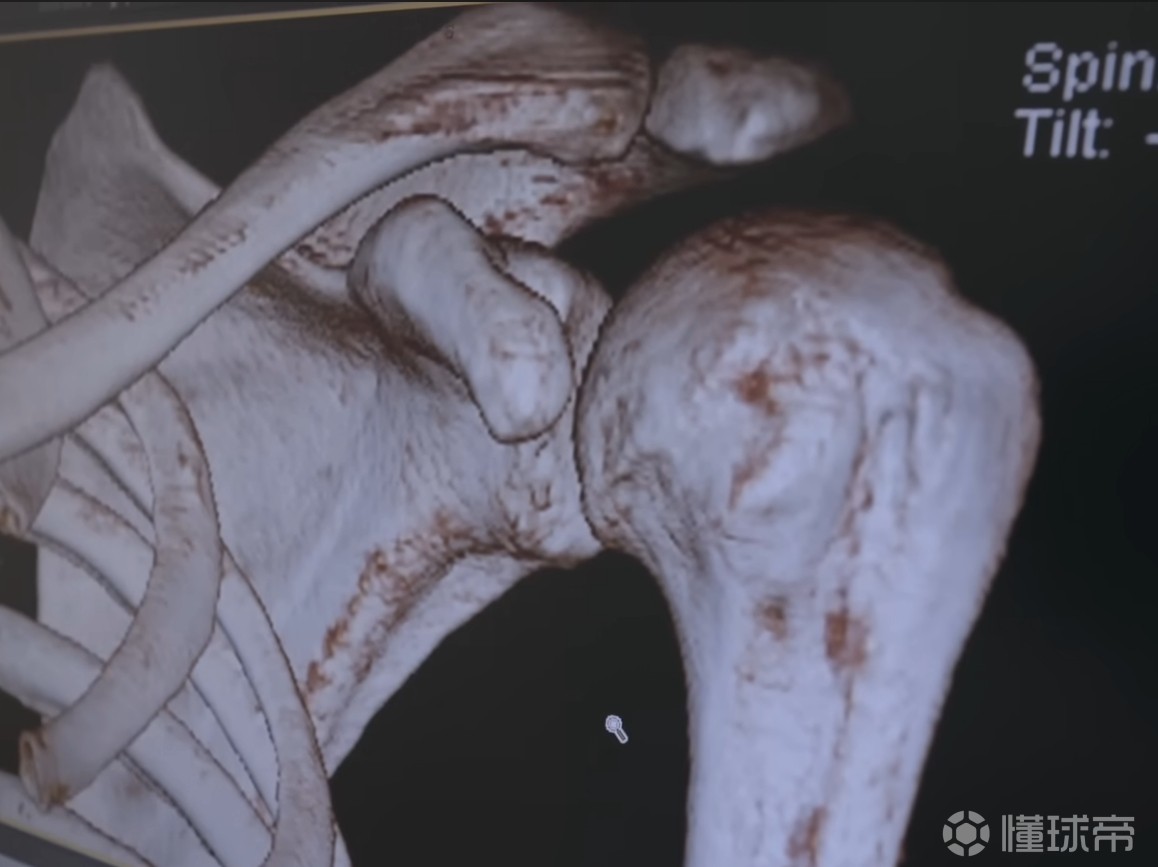

医生:当我们再次查看轴向视图时,可以看到肩膀下方这个角落的骨头有些缺损。